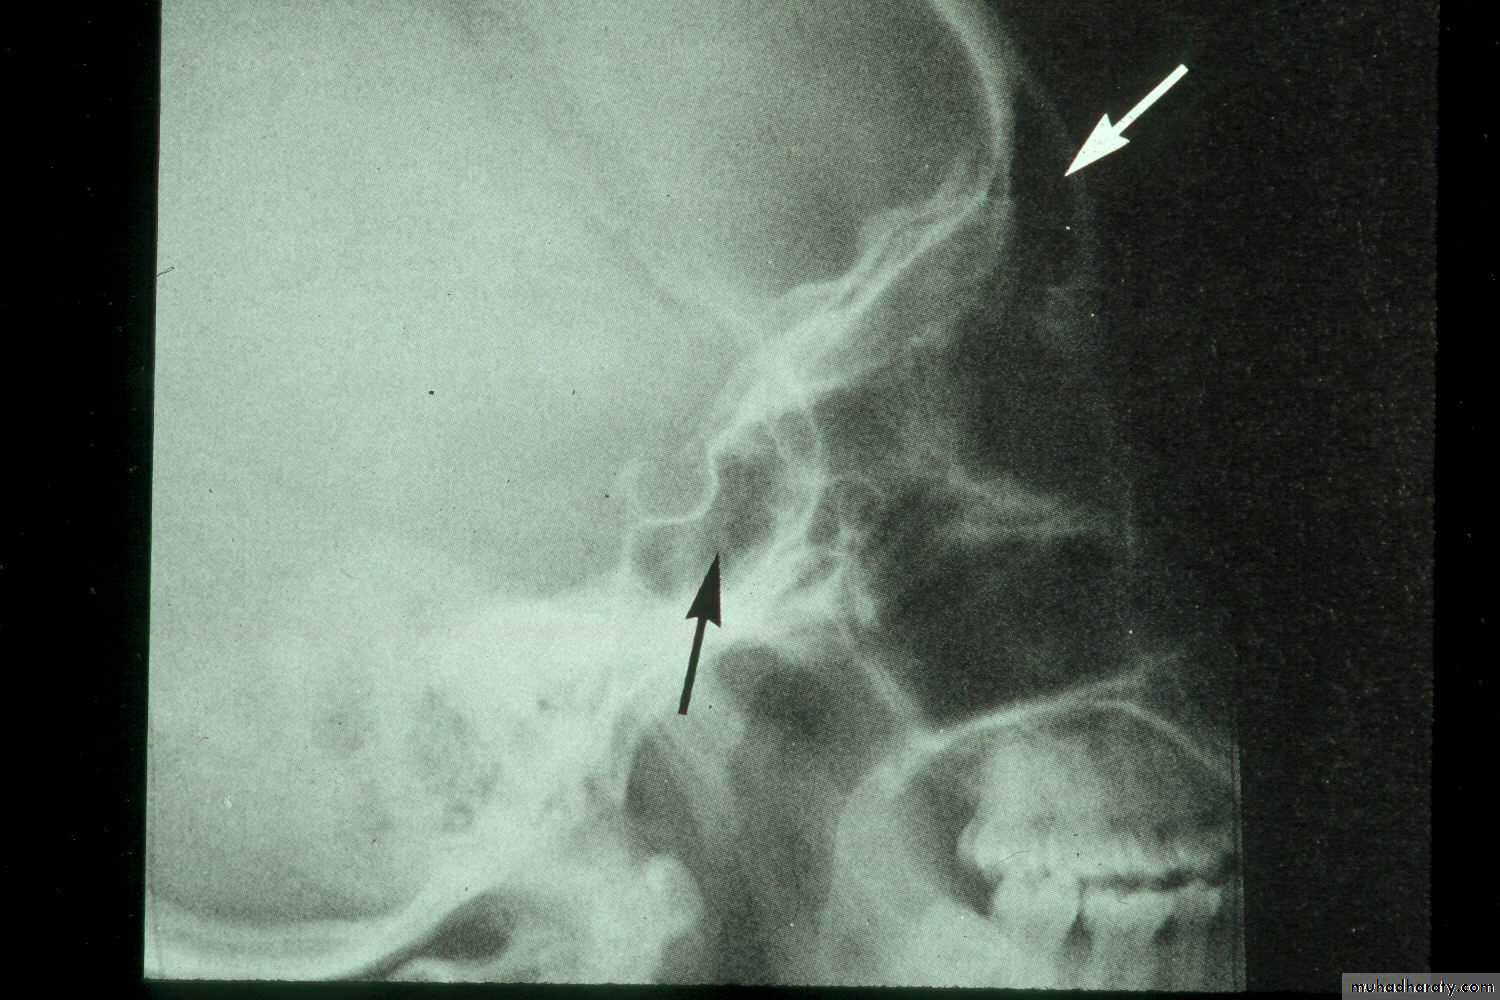

• Lateral Skull: (i) confirming the presence of fluid level and cyst (ii) in localizing a foreign body, e.g. root; particularly when the foreign body is located higher up in the sinus.

Lateral view of normal frontal and sphenoid sinuses

Hypoplastic left frontal sinus and nosocomial right maxillary sinusitis